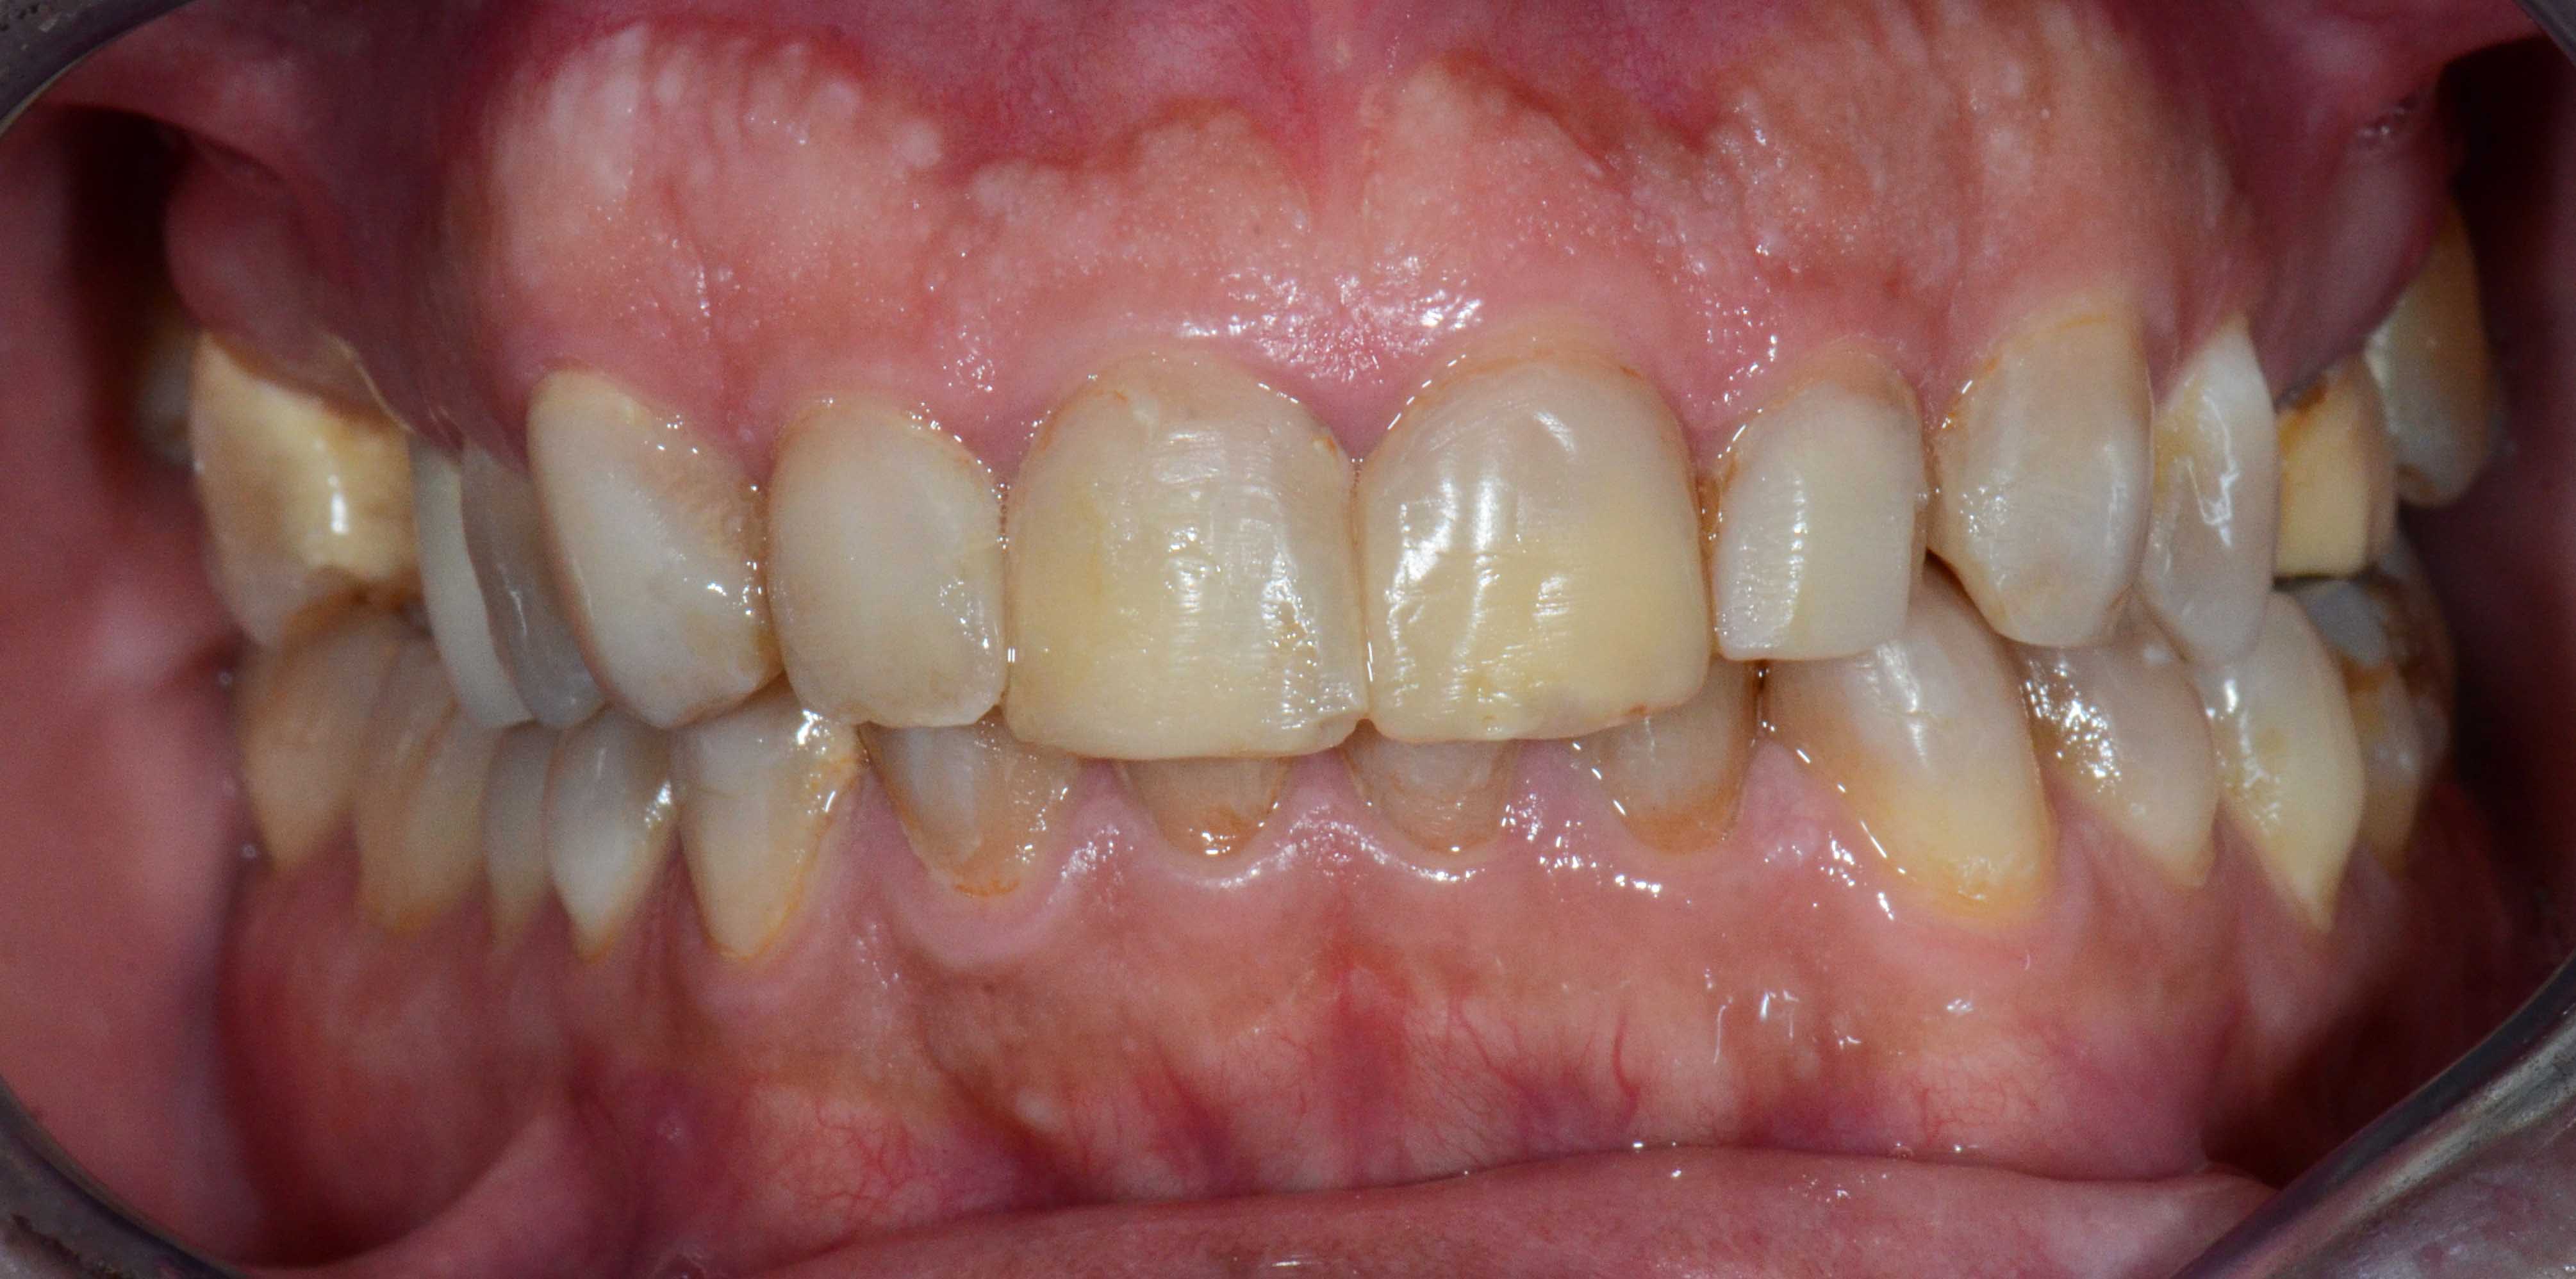

Tooth discoloration caused by tetracyclines

Main problem:

Colour changes due to the use of tetracyclines as a child. Various treatments were done before to try to solve the problem but all of them were unsuccessful.